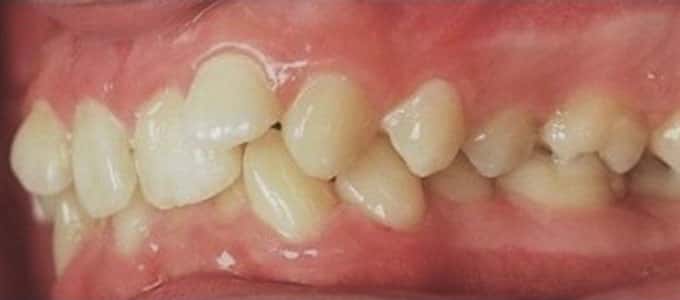

Un zâmbet frumos este roada tratamentului ortodontic de succes dar pentru a se ajunge la acest rezultat sunt necesare mai multe etape care trebuie parcurse pas cu pas.

Tratamentul ortodontic este un proces biologic complex care include modificări ale oaselor maxilare, faciale și ale țesuturilor moi pe măsură ce dinții sunt mișcați în noile poziții.

Tratamentul ortodontic nu este o soluție rapidă. Acesta începe întotdeauna cu o examinare minuțioasă a dinților, a buzelor și a întregului aspect facial, sunt necesare radiografii si fotografii de diagnostic. Din aceste informații detaliate medicul ortodont dezvoltă un plan de tratament personalizat.